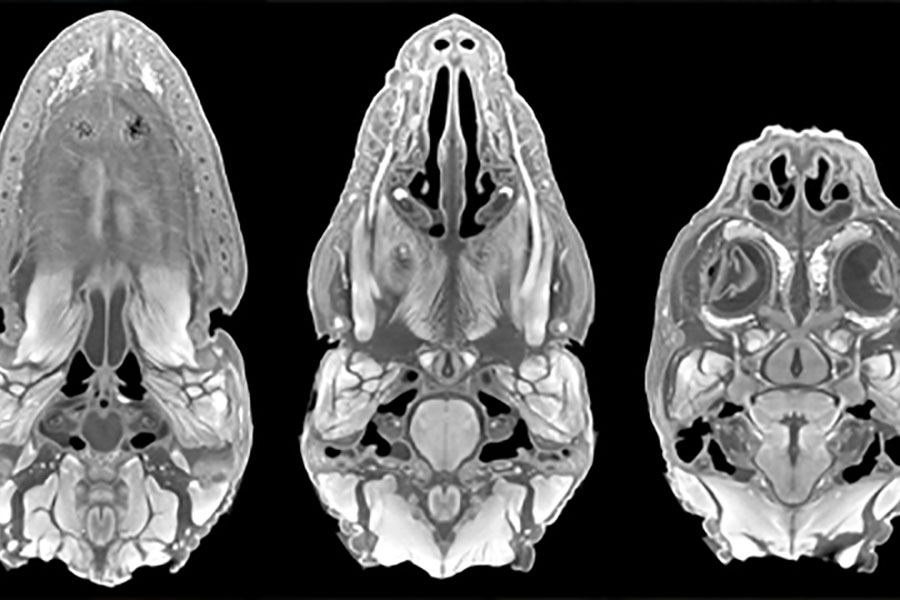

Students in the anatomy and paleontology track receive structured training to equip them for careers teaching medical gross anatomy, development, histology, and neuroanatomy. Taking courses alongside the first-year medical students and progressing into teaching assistantships, graduate students develop and hone their anatomical knowledge and instructional skills.